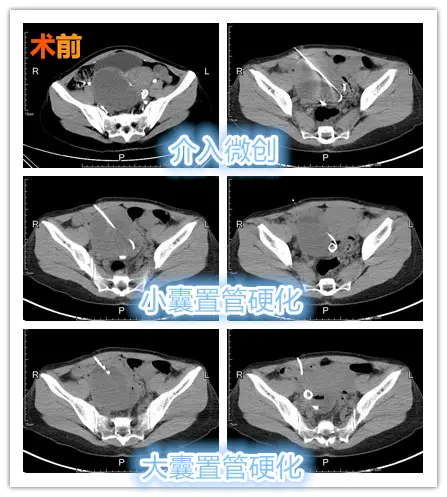

2. 囊肿大小: 囊肿大小也会对囊肿引流时间产生影响。较小的囊肿(直径小于2 cm)一般可以在短时间内引流出来,如24小时内。而较大的囊肿,特别是病灶较深或者囊壁较厚的囊肿,则可能需要更长时间进行引流。

3. 引流方式: 囊肿引流方法包括穿刺引流、外科手术引流等多种方式。穿刺引流一般引流出的时间较短,可在几小时内完成;而外科手术引流则通常需要更长的时间,有时需要留置引流管几天才能全部引流出来。